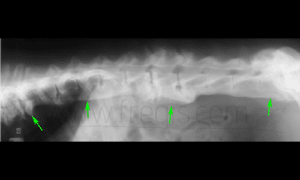

Radiographie de la colonne vertébrale d’un chien atteint de spondylarthrose déformante (becs de perroquet) très étendue.

Chez l’Airedale, l’affection est fréquente et souvent bien supportée. Elle peut être associée à une maladie des disques intervertébraux. (Levine et al. 2006).